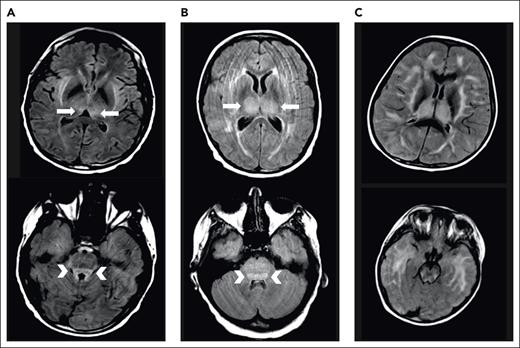

We typically administer thiamine repletion in the setting of severe CRS or ICANS. During severe ICANS, MRI changes resembling those in Wernicke encephalopathy, with T2/FLAIR hyperintensities in the dorsomedial thalami and tectal plate, have been reported12 (Figure 1). We have found abnormally low thiamine levels in hospitalized patients requiring CAR T-cell therapy. Inflammation is thought to be a factor driving thiamine-deficient state, and patients with sepsis are frequently thiamine deficient.50 Thiamine deficiency decreases BBB competence.51 We supplement patients experiencing severe CRS or ICANS with high-dose thiamine for 3 days, followed by daily thiamine until CRS and ICANS resolve.

Examples of MRI changes during severe ICANS. Brain MRI during severe ICANS may rarely demonstrate symmetric T2/FLAIR hyperintensities in dorsal medial thalami (top; arrows) and tectal plate (bottom; arrowheads) resembling imaging changes associated with Wernicke encephalopathy. (A) MRI images from an adult patient with grade 4 ICANS. (B) MRI images from a pediatric patient with grade 4 ICANS. (C) Images from a pediatric patient with diffuse cerebral edema.